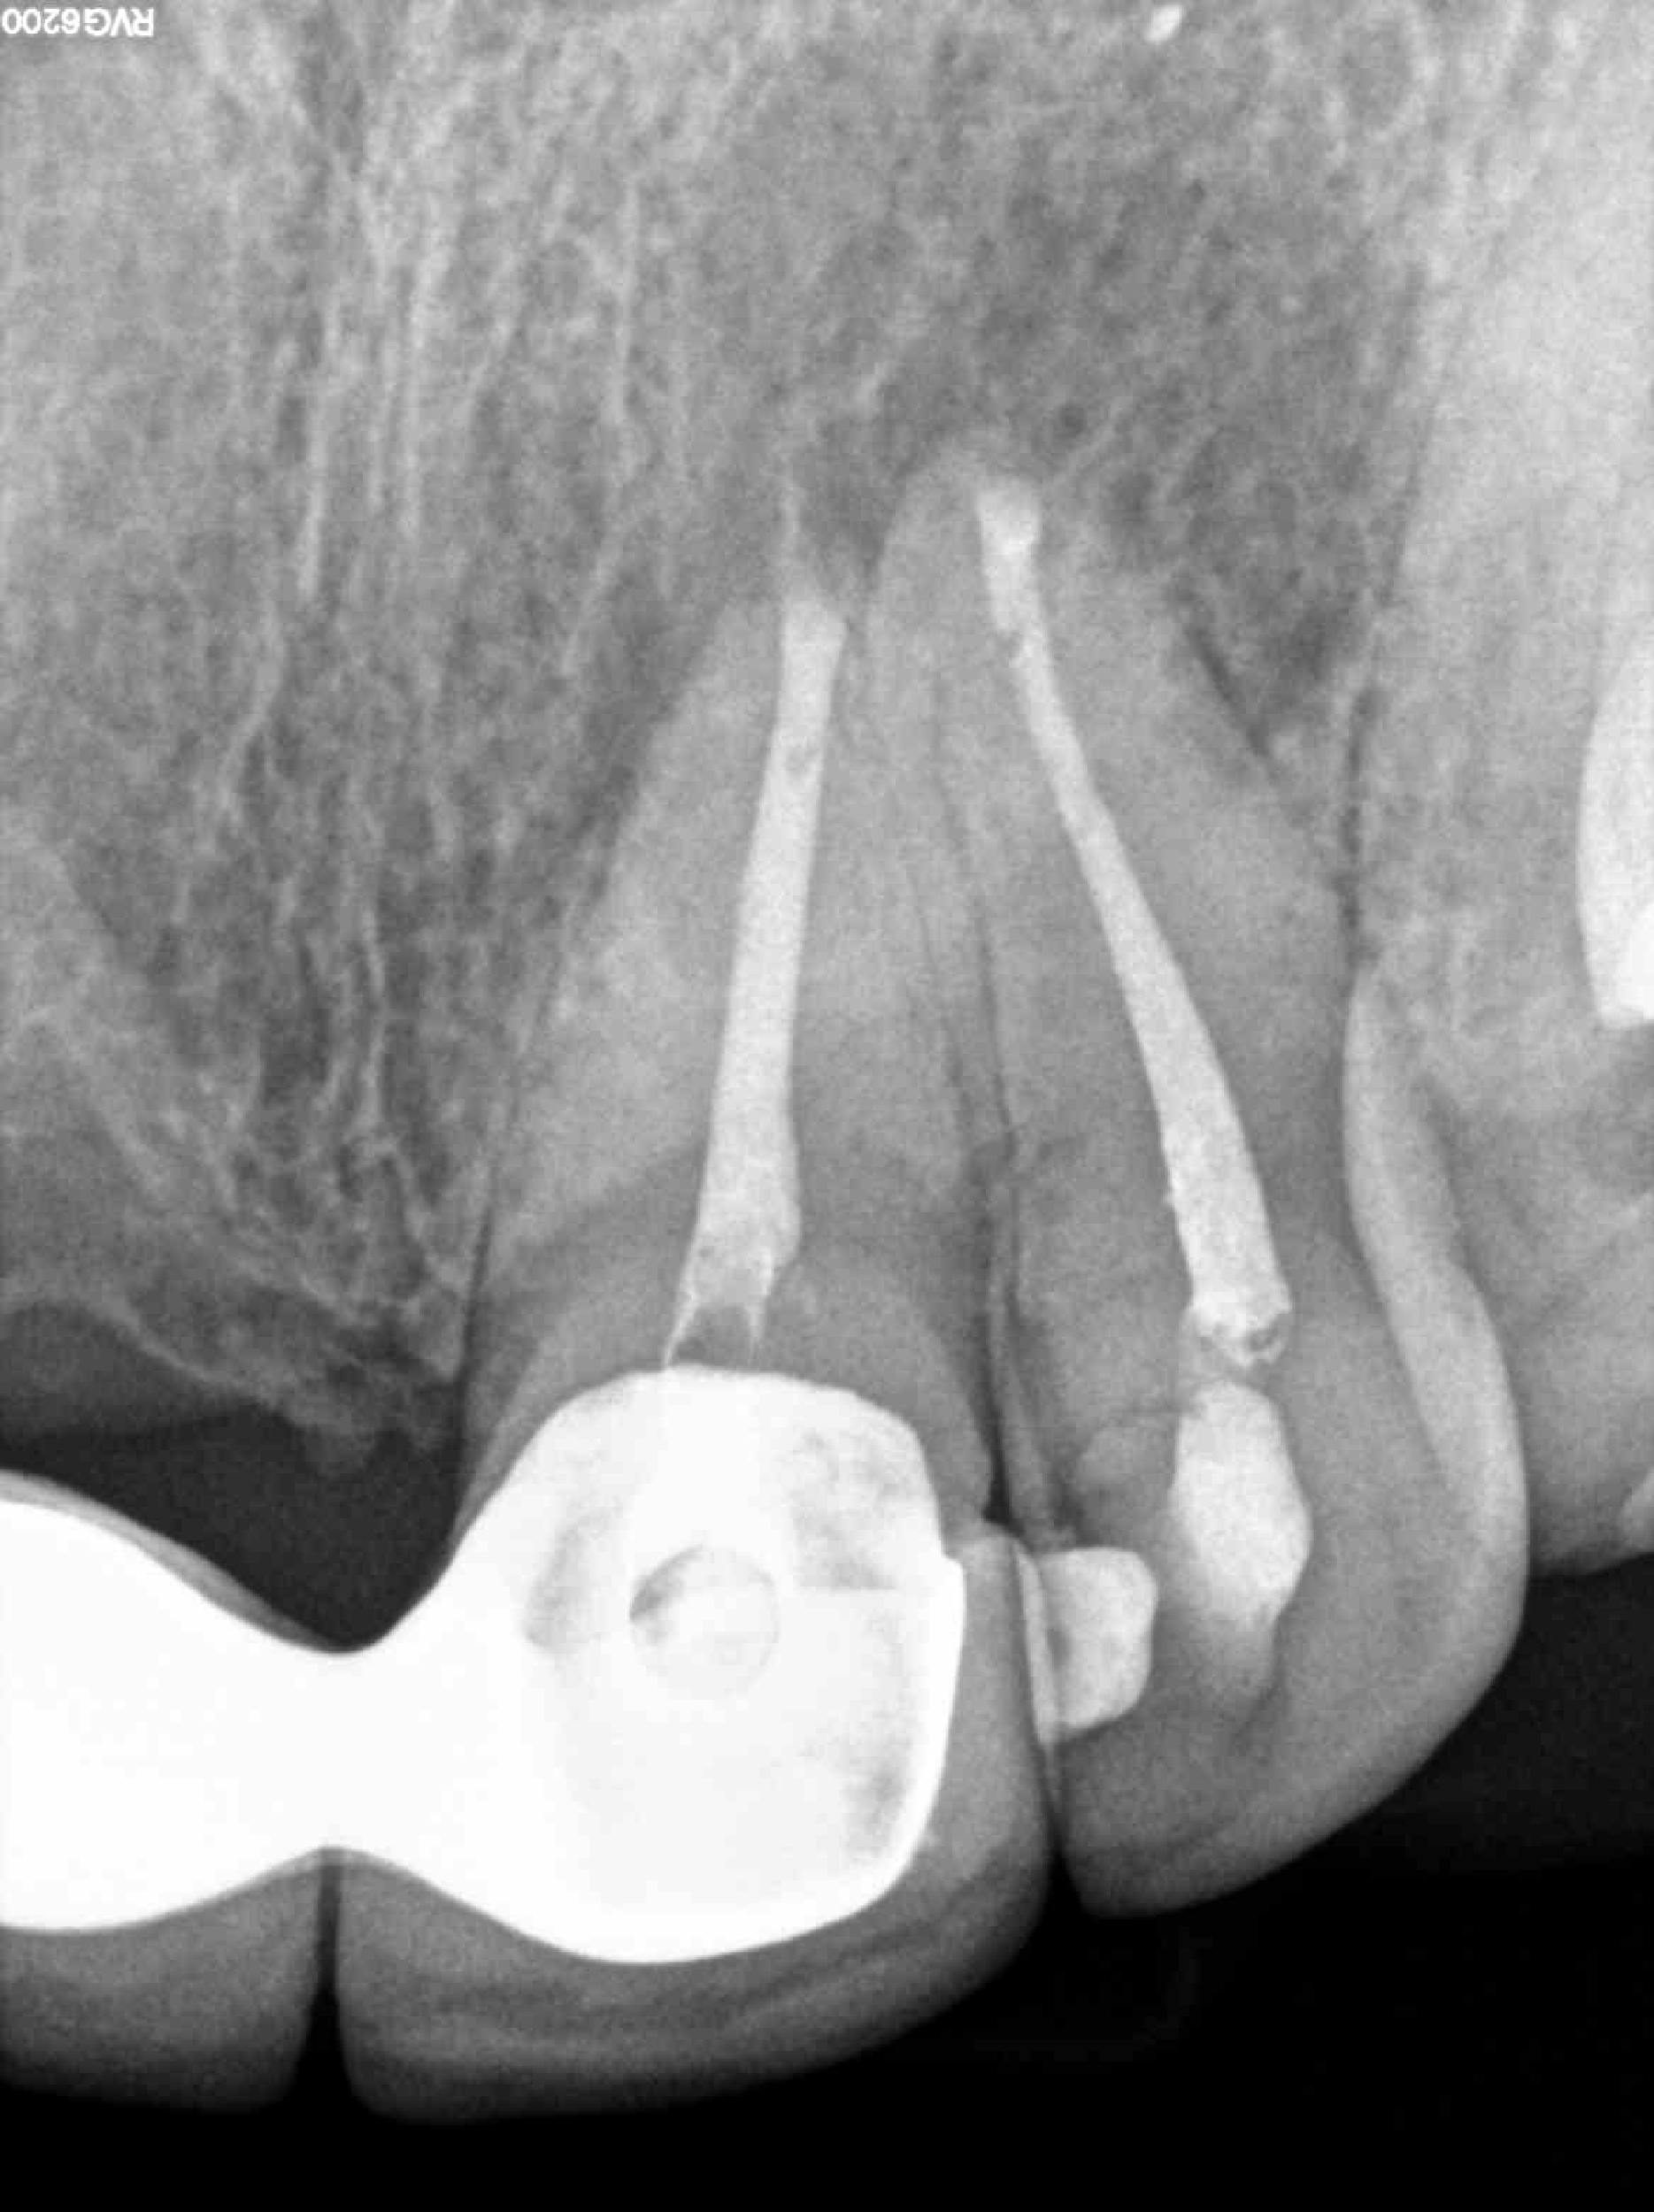

2.1 y 2.2 Apicectomia

Año 2023

Radiografías